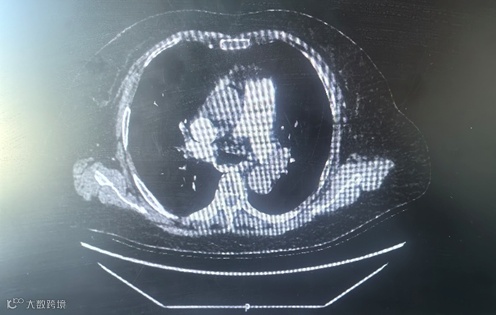

术前CT

现病史:患者因“阵发性胸闷、气短2月余,伴胸痛4日”⼊院。急诊完善相关检查 ,D-⼆聚体 2230 ng/mL,BNP 1288pg/L,肌钙蛋白I 0.18ng/mL ,双下肢血管彩超提示“双侧下肢浅静脉迂曲增宽并血栓形成”,心脏彩超提示“右心及左房扩大、肺动脉高压(轻度)、EF:33%”,肺动脉增强 CT 提示“双侧肺动脉主干及其分支多发栓塞”,明确诊断为“ 急性肺栓塞” 。